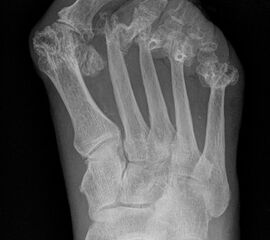

Es handelt sich bei dem „rheumatischen Vorfuß“ nicht um eine „normale“, meist rein mechanische Metatarsalgie, sondern um eine durch Synovialitiden sich häufig schnell entwickelnde und sehr ausgeprägte komplexe Fehlstellung. Die persistierend chronische Entzündung mit hoher Aktivität führt zu einer Veränderung oder Verlust der Sehnenfunktion mit Ruptur der plantaren Platte und Ligamente, subchondralen Usuren, Knorpel- und Knochendeformationen. (siehe auch Kapitel "Die Stainsby OP" von Briggs P, Stainsby D - Abschnitt "Pathomechanik des deformierten Rheumafußes").

Durch die verbesserte medikamentöse Rheumatherapie sind diese ausgeprägten Knochendestruktionen rückläufig. Die Indikation zur Resektionsarthroplastik mit Entfernung der Metatarsale II-V Köpfchen wird damit seltener 56. Auch bei nur teilweise erhaltenen Gelenken sollte in der modernen Rheumafußchirurgie einem gelenkerhaltenen Verfahren der Vorzug gewährt werden, da der Gelenkerhalt mit besseren funktionellen Ergebnissen korreliert 7. Allerdings werden auch noch heute schwere Gelenkdestruktionen beobachtet, da ein Teil der Patienten auf die medikamentöse Therapie unzureichend anspricht oder die Therapien nicht wahrnimmt.